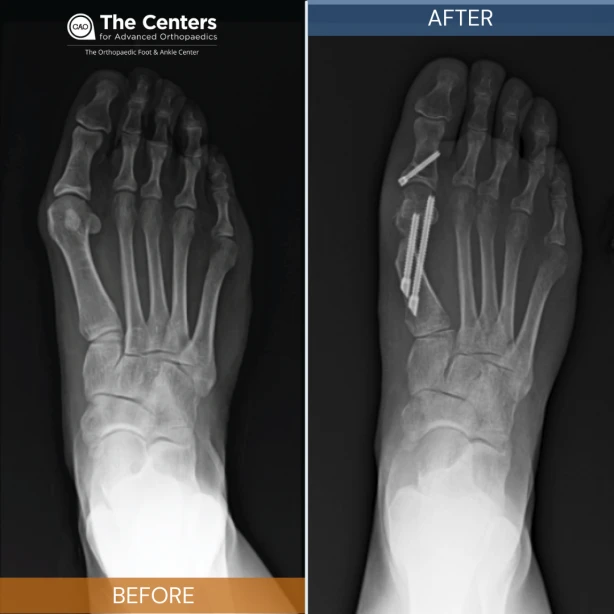

A bunionectomy is a surgical procedure used to remove a bunion and can help relieve pain.

Minimally Invasive Incisions vs. Traditional Incisions